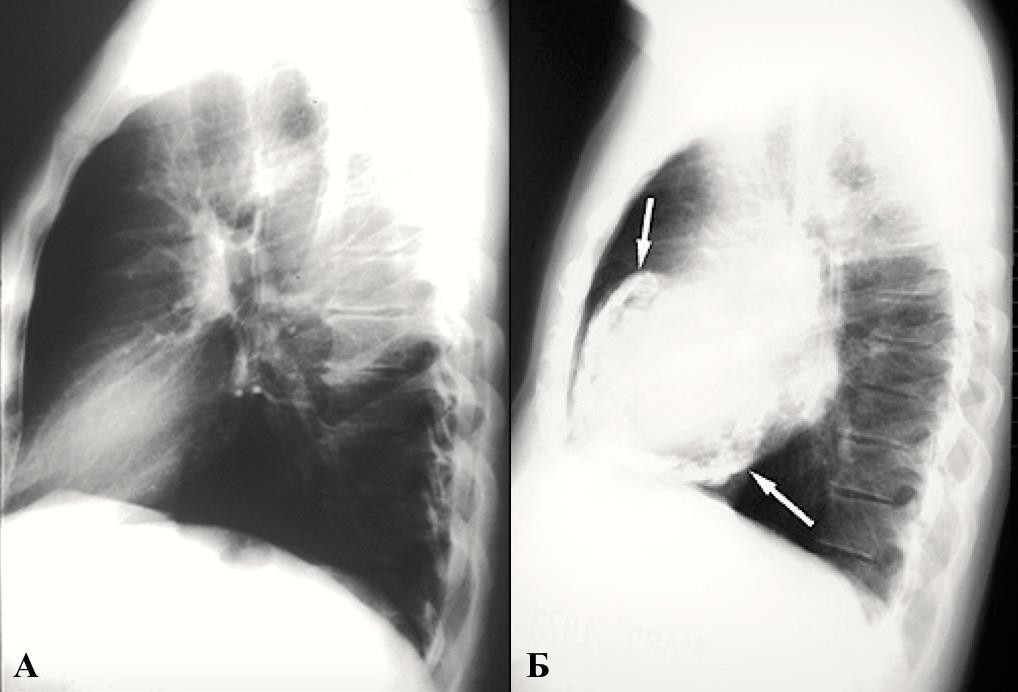

При констриктивном перикардите маленькое «неподвижное» сердце не меняет своего расположения при изменении положения тела или при дыхательной экскурсии. Сжатое сердце теряет свою талию и дифференциацию дуг, появляется неровность контуров, обусловленная многочисленными сращениями в перикардиальной полости.

Выявляются небольшие желудочки при одновременном увеличении предсердий. Характерно отсутствие застоя по малому кругу.

Развитие «панцирного» сердца происходит в 25% случаев констриктивного перикардита. Обызвествленные участки лучше определяются на боковой и передней косой проекциях (Приложение А3, рис. 10) [1, 3].